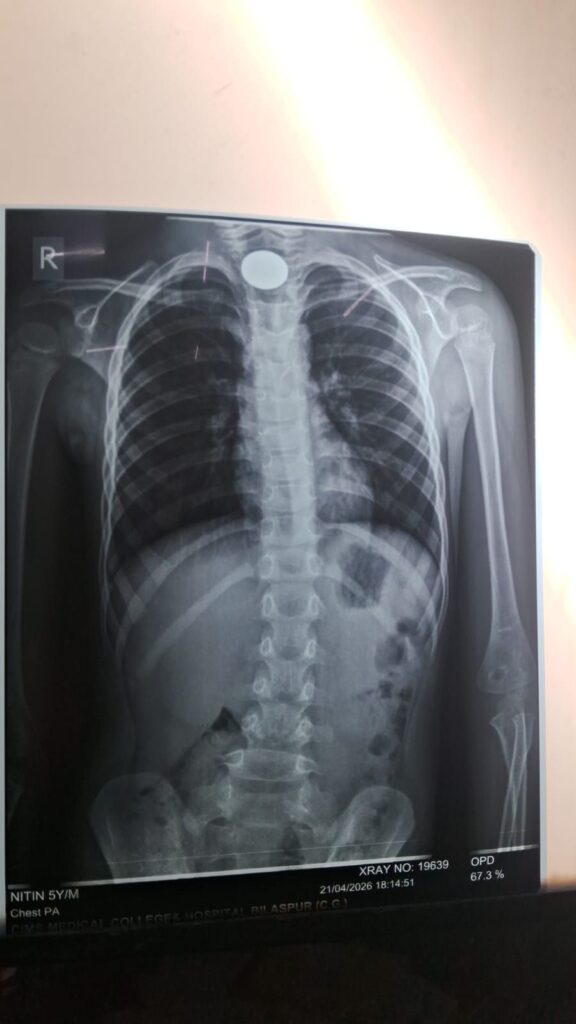

जानकारी के अनुसार, चिरमिरी जिले के धवलपुर निवासी 5 वर्षीय नितिन सिंह ने खेलते-खेलते पांच रुपये का सिक्का निगल लिया, जो उसके गले में जाकर फंस गया। सिक्का श्वसन मार्ग के पास अटक जाने के कारण बच्चे को सांस लेने में गंभीर परेशानी होने लगी और उसकी हालत तेजी से बिगड़ने लगी।

बच्चे की नाजुक स्थिति को देखते हुए उसे तुरंत ऑपरेशन थिएटर में शिफ्ट किया गया, जहां अत्याधुनिक एंडोस्कोपिक तकनीक का उपयोग करते हुए बिना किसी बड़े चीरे के सिक्के को सावधानीपूर्वक बाहर निकाला गया। पूरी प्रक्रिया के दौरान एनेस्थीसिया टीम ने बच्चे की सांस और जीवनरक्षक संकेतों पर लगातार नजर बनाए रखी।